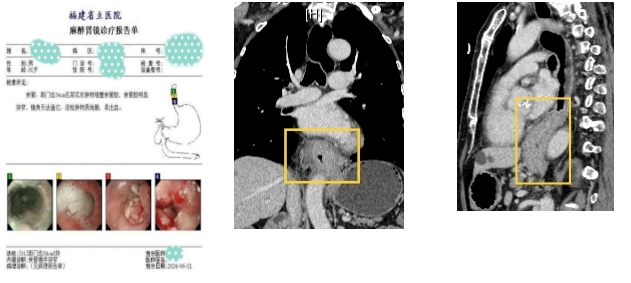

91岁的王依伯,近半年来总觉得自己吃东西的时候被胸口的东西挡住了。他在当地医院挂瓶输液后,不见好转,最近已经发展到完全吃不下饭、只能喝水的程度。家人把王依伯送到了我院金山院区,胸外科徐驯宇主任医师团队接诊后,通过胃镜检查,发现他为食管下段的腺癌,已经出现梗阻的症状

以往对这样的患者,医生通常会对其进行胃造瘘以维持营养,然后采取放疗和化疗等保守的方法改善症状。负责接诊的黄郴副主任通过对王依伯的评估发现,老人家虽然已91岁高龄,但是生活仍然可以自理,每天还能出去散步,心肺功能的评估也远好于预期,并且王依伯本人非常愿意通过手术来达到正常进食的目的

经过与麻醉科、重症医学科的多学科会诊讨论以及与患者和家属的反复沟通,最终决定对王依伯进行手术治疗。麻醉科吴晓丹主任医师、吴海星副主任医师为王依伯制定了周密的麻醉计划以保证手术中的生命征平稳。手术当天,根据王依伯的肿瘤位于食管下段的特点,徐驯宇主任医师摒弃了常规的右胸、腹部、左颈的三切口路径,转而采用经左胸一个切口的手术方式完成了肿瘤切除、消化道重建的步骤,使得整个手术仅耗时两个半小时,同时避免了对上段食管及喉返神经的骚扰而造成的术后反流及喉返神经损伤。